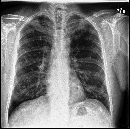

Disease-aware image editing by means of generative adversarial networks (GANs) constitutes a promising avenue for advancing the use of AI in the healthcare sector. Here, we present a proof of concept of this idea. While GAN-based techniques have been successful in generating and manipulating natural images, their application to the medical domain, however, is still in its infancy. Working with the CheXpert data set, we show that StyleGAN can be trained to generate realistic chest X-rays. Inspired by the Cyclic Reverse Generator (CRG) framework, we train an encoder that allows for faithfully inverting the generator on synthetic X-rays and provides organ-level reconstructions of real ones. Employing a guided manipulation of latent codes, we confer the medical condition of cardiomegaly (increased heart size) onto real X-rays from healthy patients. This work was presented in the Medical Imaging meets Neurips Workshop 2020, which was held as part of the 34th Conference on Neural Information Processing Systems (NeurIPS 2020) in Vancouver, Canada